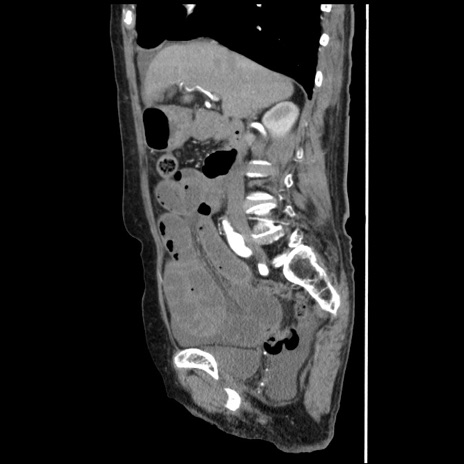

冠状断像

【症例】80歳代女性

【主訴】腹痛

【現病歴】8時間前から腹痛あり来院。

【既往歴】糖尿病、脂質異常症、子宮体癌にて子宮全摘術

【身体所見】意識清明・会話良好だが腹痛で苦悶様、全腹部にわたって反跳痛と圧痛あり

【データ】WBC 13600、CRP 0.14、LDH 224、CK 90